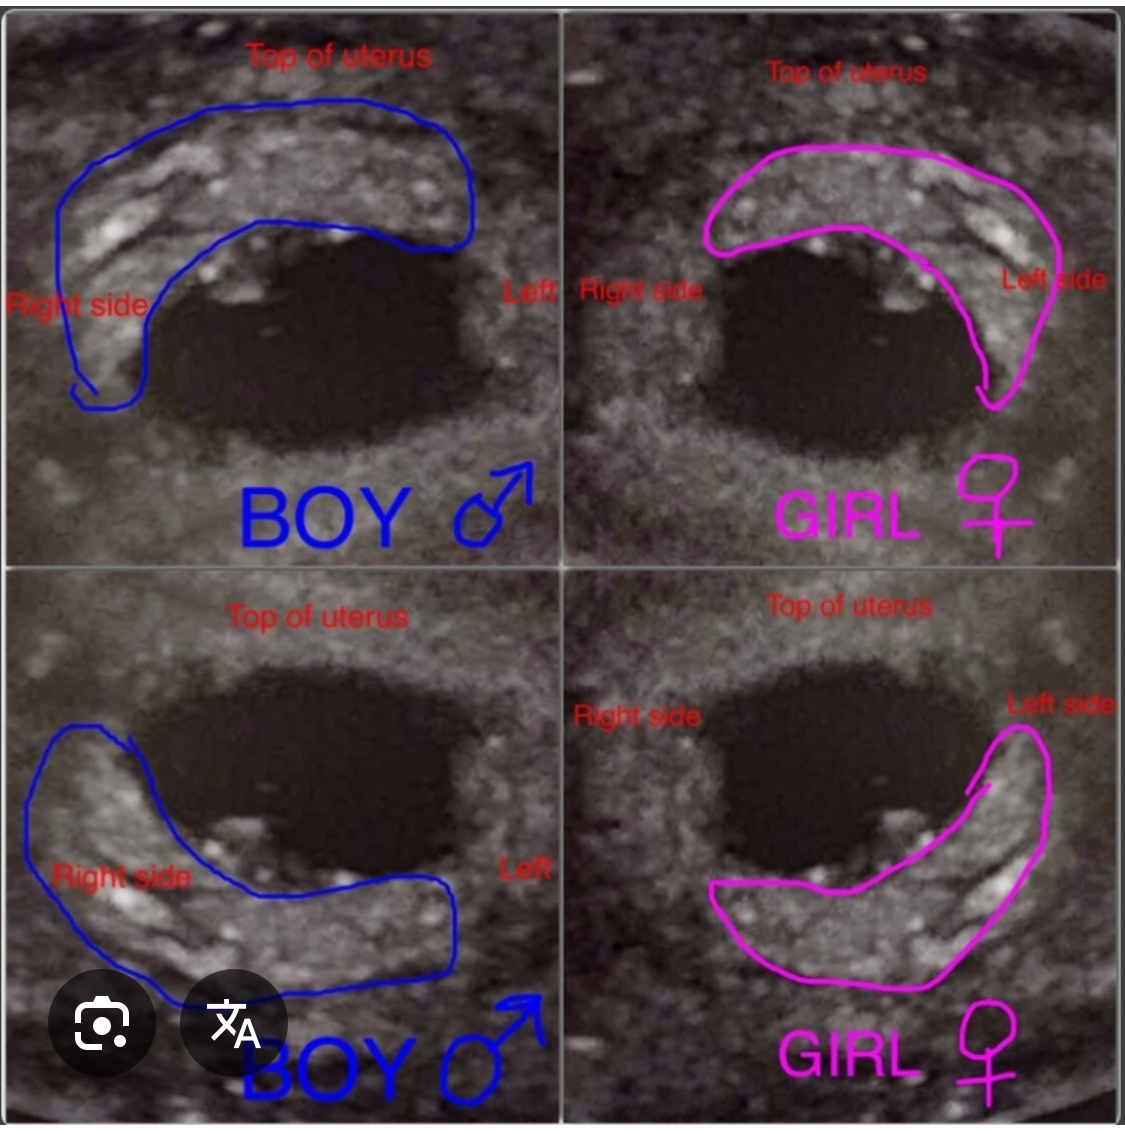

Я сравнивала вот по такому фото, у меня совпало :))) Девочка Изображение